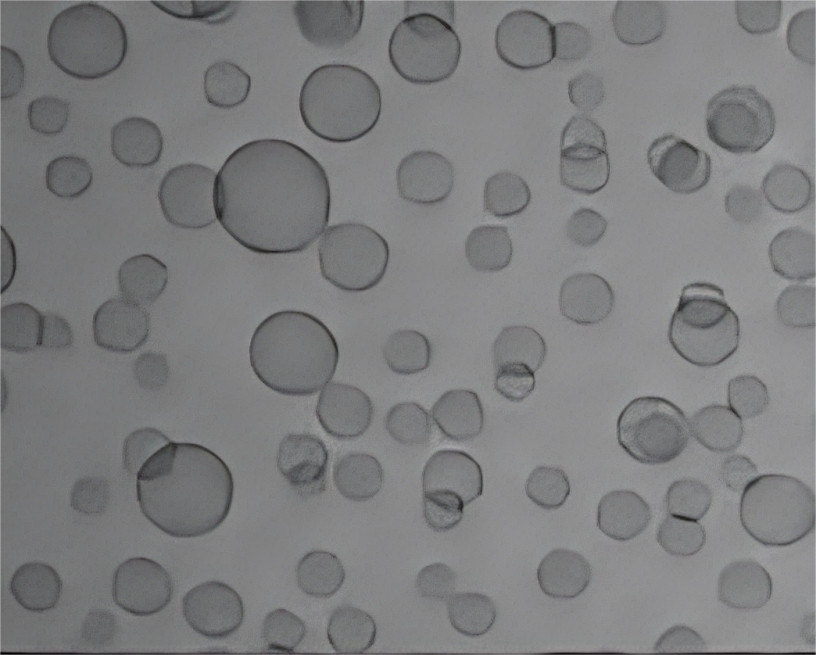

Figure. Permeation into the epidermis and retention within the dermis. The data show that GLYCEROSOMES significantly increase drug retention in the stratum corneum and epidermis compared to conventional liposomes, demonstrating improved localized skin delivery.